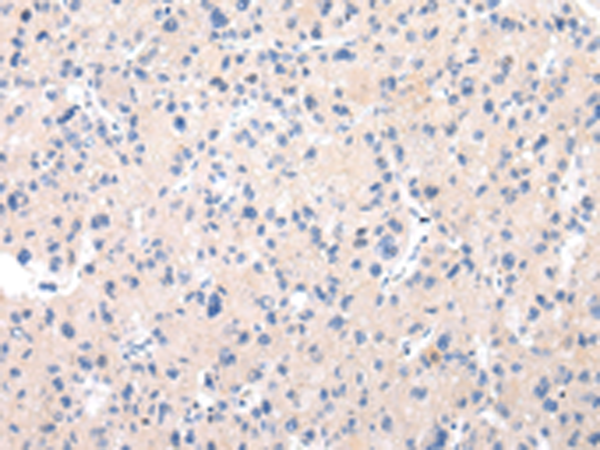

分类: 科研抗体货号: P12455别名: MG2应用: IHC反应种属: Human